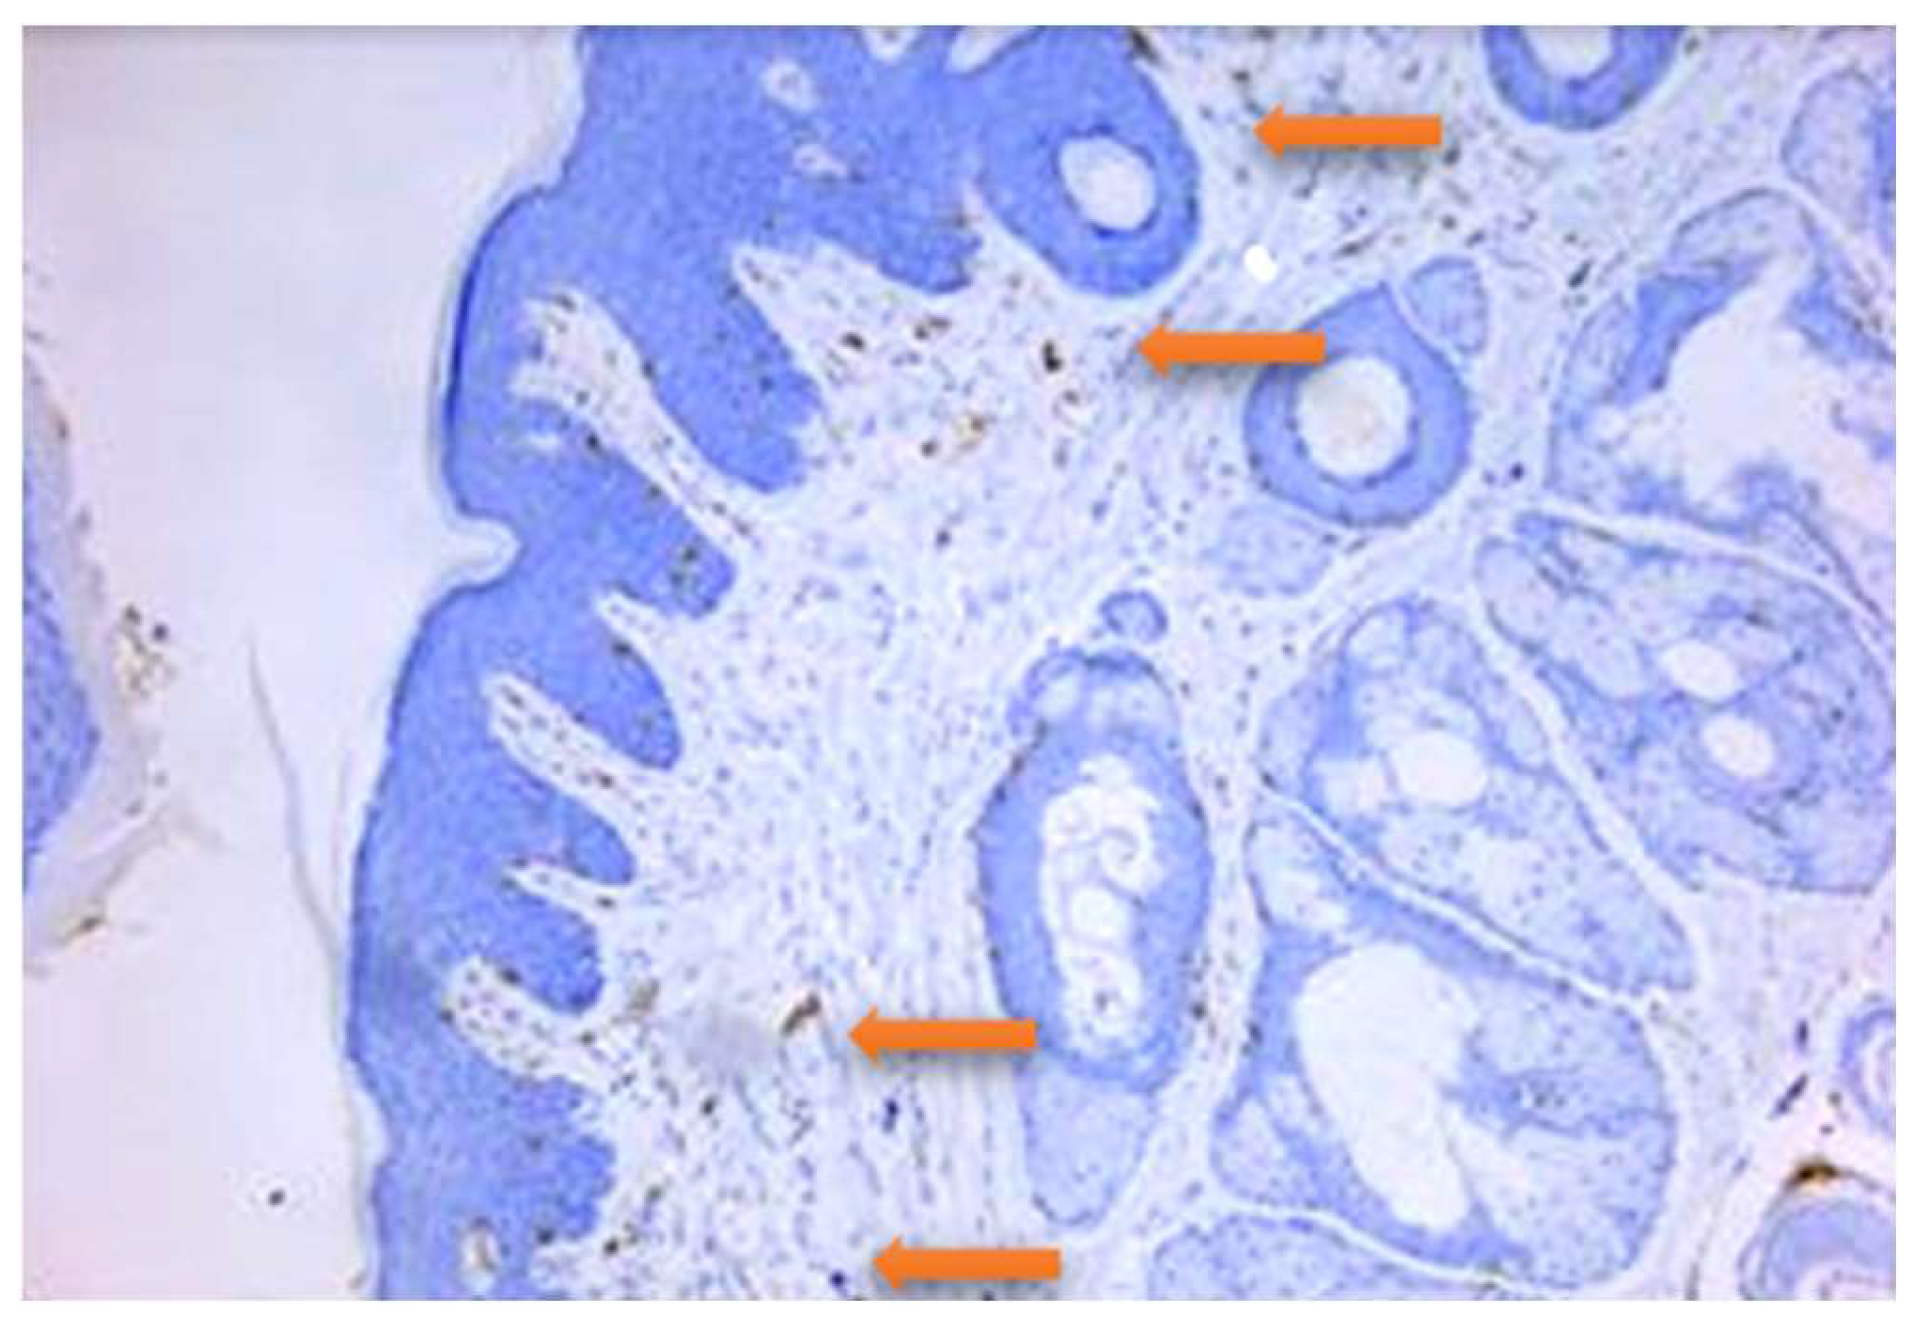

- Roi, C.; Gaje, P.N.; Ceaușu, R.A.; Roi, A.; Rusu, L.C.; Boia, E.R.; Boia, S.; Luca, R.E.; Riviș, M. Heterogeneity of Blood Vessels and Assessment of Microvessel Density-MVD in Gingivitis. J. Clin. Med. 2022, 11, 2758. [Google Scholar] [CrossRef]

| Antibody | Epitop/Marker | Manufacturer | Antigenic Unmasking | Dilution |

|---|---|---|---|---|

| CD3 | T lymphocytes | DAKO | Citrate buffer pH = 6 | 1:100 |

| CD20 | B lymphocytes | DAKO | Citrate buffer pH = 6 | 1:50 |

| CD34 | Endothelial cells | DAKO | Citrate buffer pH = 6 | 1:50 |

| Group | T CD3+ Cells | B CD20+ Cells | Total CD34+ Cells | Mature CD34+ Cells | Imature CD34+ Cells |

|---|---|---|---|---|---|

| Control | 3 | 2.5 | 17.5 | 7 | 10.5 |

| DP | 55.5 | 6 | 13.5 | 4 | 9.5 |

| DPCu | 41 | 3.5 | 25 | 4.5 | 20.5 |

| DPR | 15 | 6.5 | 7 | 2.5 | 4.5 |

| DPCuR | 2 | 0.5 | 8 | 3 | 5 |